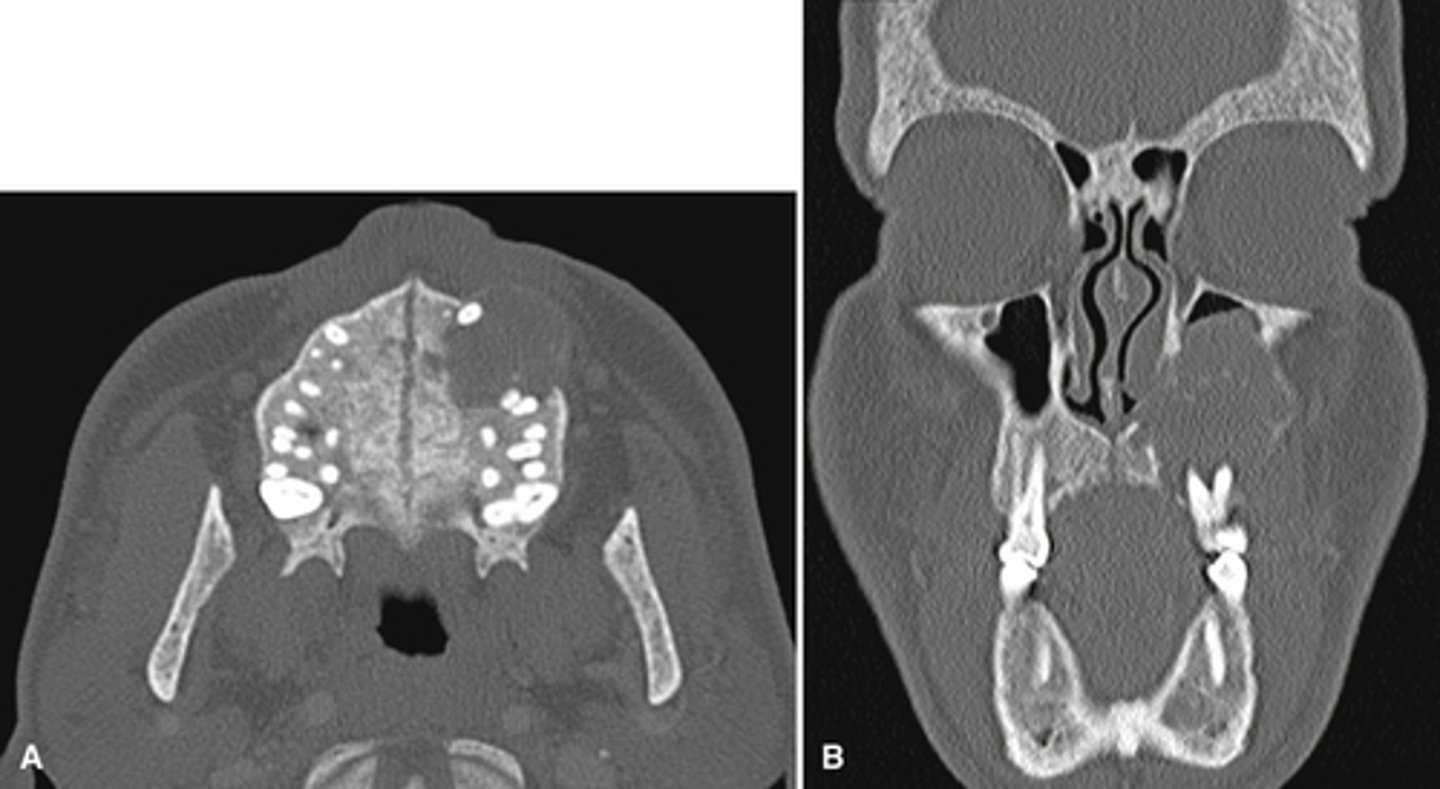

The bottom radiographs depict a developing 7year-old child.

1. The cortication of all the articulating surfaces are thin.

2. The mandibular fossa is shallow

3. The articular eminence is short

The top images are being compared to the bottom images, which patient is younger and what are all the ways to know this.